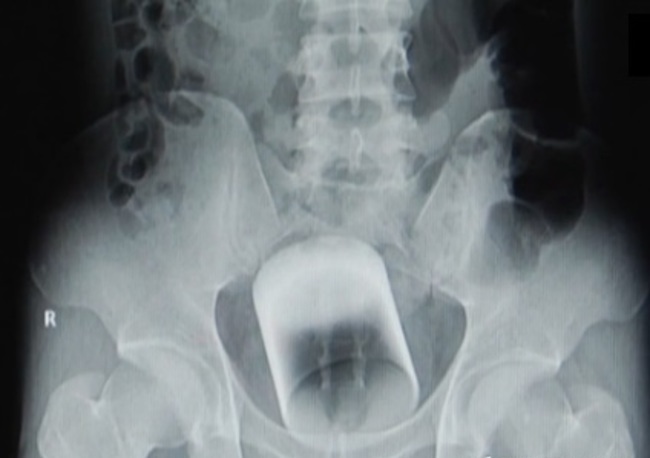

gif_animation オナニーの数倍気持ちいと言われる「肛門オナニー」をやり過ぎた男の末路。”抜けない” と病院を訪れた男のお尻からは、直径7cmのコップが摘出された。[5]img